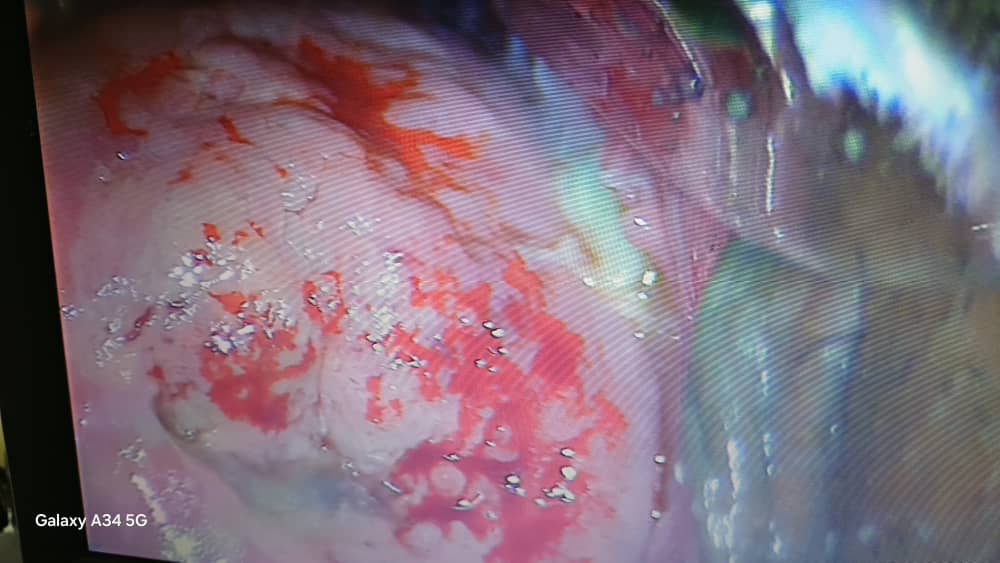

در این بخش عکسها و گزارشهای واقعی از جراحیهای هفتگی ارائه میشود تا بیماران با روند تشخیص و درمان فوقتخصصی ضایعات پیشسرطانی و سرطانهای زنان آشنا شوند.

لیزر درمانی در زگیل و ضایعات پیشسرطانی زنان

لیزر درمانی روش کمتهاجمی برای حذف زگیل تناسلی و برداشت ضایعات پیشسرطانی زنان است که به پیشگیری از سرطان و بهبود سریع کمک میکند.